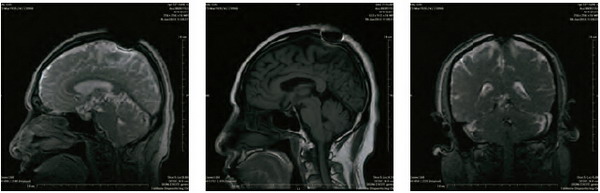

开初仁波且MRI核磁共振脑断层扫描医学图片

这是开初仁波且修金刚换体禅后,在加州医疗中心检查身体时拍摄的MRI核磁共振检测照片。可以清晰看见开顶后,头顶大乐轮门处头骨、皮肉等大开,开口宽约两英寸,脑髓开出鸡蛋大的凹洞。更令人震撼的是,当开初仁波且拍摄扫描照片时,整块头骨突然不见,而呈现出弥勒菩萨乳胎婴童像,身搭俱袍,手脚呈现,心空大洞,跏趺而坐,在电脑上清晰可见五官面容,眼睛、鼻子、嘴巴。